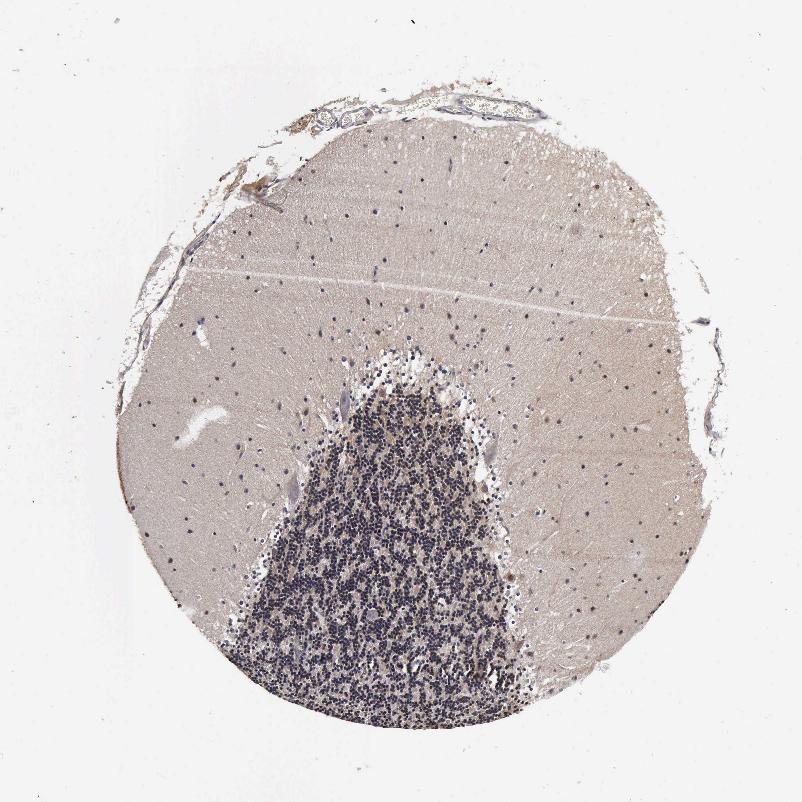

CEREBELLUM - Antibody stainingi

Antibody staining in the annotated cell types in the current human tissue is reported as not detected, low, medium, or high, based on conventional immunohistochemistry profiling in selected tissues. This score is based on the combination of the staining intensity and fraction of stained cells.

Each image is clickable and will lead to virtual microscopy that enables deeper exploration of all samples and also displays staining intensity scores, fraction scores and subcellular localization as well as patient and tissue information for each sample.

Antibody HPA041344Antibody HPA049132Antibody CAB000362Antibody CAB005419

Purkinje cells Not detectedMediumNot detectedNot detected

Cells in granular layer Not detectedHighNot detectedLow

Cells in molecular layer Not detectedHighNot detectedNot detected